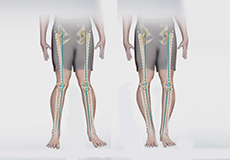

Knee Angular Deformities

Angular deformities of the knee are variations in the normal growth pattern during early childhood and are common during childhood.